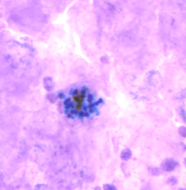

ENTAMOEBA HISTOLYTICA TROPHOZOITE

Professor: Dr. Glena Fe A. Yapchulay-Alcabasa